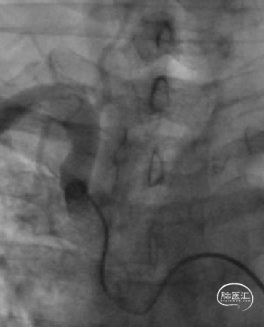

主动脉弓造影

成功穿刺左侧远桡动脉后,置入6.5F薄壁桡动脉鞘,V18+Fastrack微导管支撑下,DA顺利进入L-V1段。